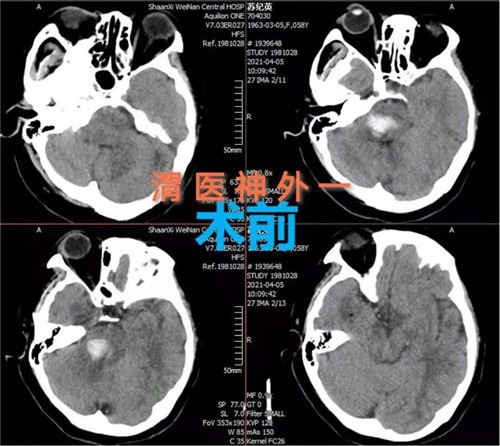

患者女性,58岁,突然意识不清3小时,行头颅CT检查提示:脑干出血。入院时患者深度昏迷,GCS评分6分。患者脑出血部位特殊,病情危重,手术风险大,并且既往有高血压、糖尿病史,围手术期随时有死亡可能。神经外科一病区赵金安主任带领团队评估手术风险,立刻上报医院,并和家属及时沟通,经反复讨论后最后决定实施开颅脑干血肿清除术:一级入路为右侧乙状窦后入路;二级入路为三叉神经下一面听神经上脑桥侧安全区。

手术计划制定后,即刻安排手术,手术麻醉科确定了由麻醉医师钟永慧、配合护师党海婷和马丹组成的麻醉护理团队。手术历时近4个小时,手术过程患者生命体征平稳,术中总出血量约50毫升,术后患者恢复自主呼吸。术后次日患者生命体征平稳,意识恢复,右侧肢体活动正常,左侧肢体活动正在恢复中。